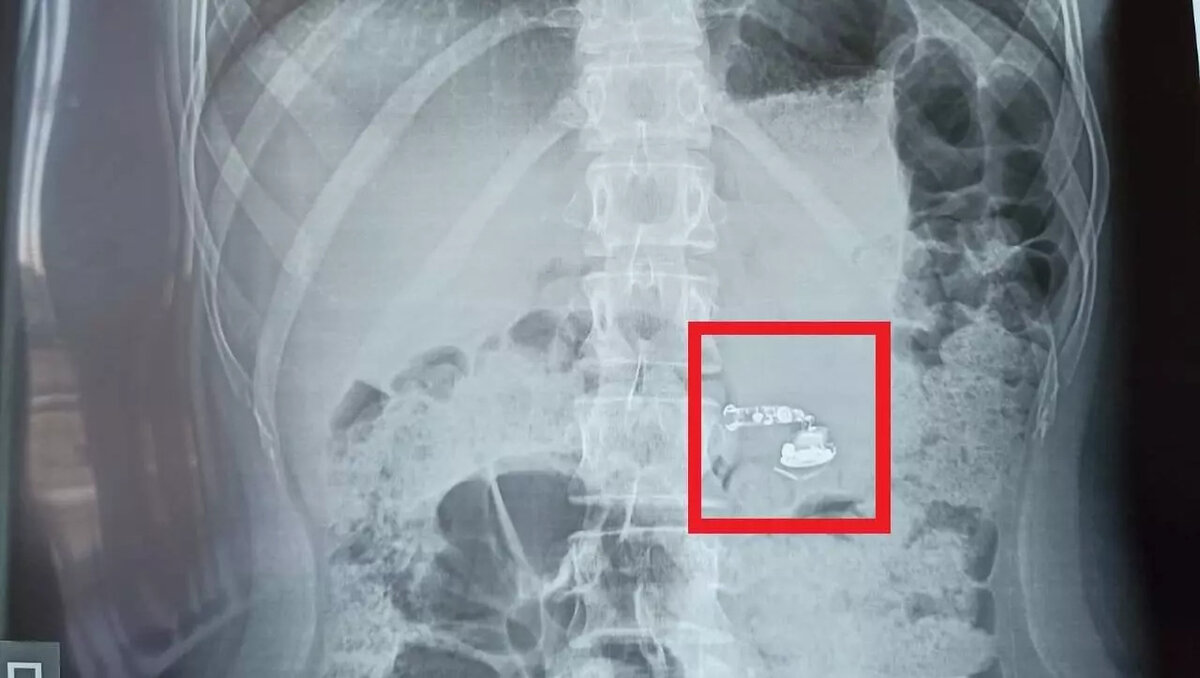

Беспроводной наушник обнаружили в желудке 15-летней школьницы из Башкирии

Девочка случайно проглотила беспроводные наушники во время сна. После пробуждения с болью в горле она была доставлена в больницу скорой медицинской помощи.

Вечером девушка заснула с наушниками в ушах. Посреди ночи она проснулась от боли в горле и поняла, что наушники исчезли. Разбудив родителей, они немедленно вызвали скорую помощь.

Подростка доставили в больницу скорой медицинской помощи, где ей провели рентген брюшной полости и фиброгастроскопию для осмотра пищевода, желудка и 12-перстной кишки. В результате обследования наушники были обнаружены в кишечнике.

В данном случае не потребовалось проведение оперативного вмешательства. Предмет естественным образом вышел из организма без осложнений.